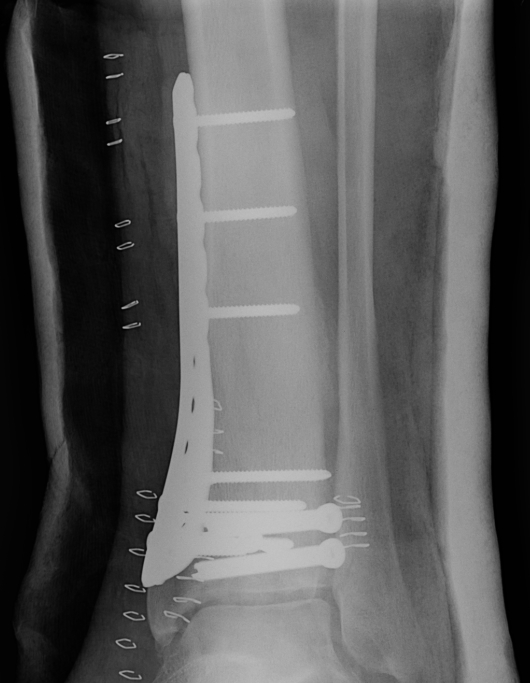

Compression plate (DCP - dynamic compression Plate)

- compression generated either by a tension device or by the dynamics of the plate itself (DCP)

- plate should be applied to the tension side of eccentrically loaded long bones

- produces fracture compression and resists tension forces

- DCP plate can produce about 600N (lag screw 2000-4000N)

- underlying bone loss due to interruption of blood supply / periosteum injury

- limited by decreasing the surface contact of the plate i.e. LCDCP (limited contact DCP)

- plate should be over bent to produce compression of the far as well as near cortex

- inner screws should be applied first